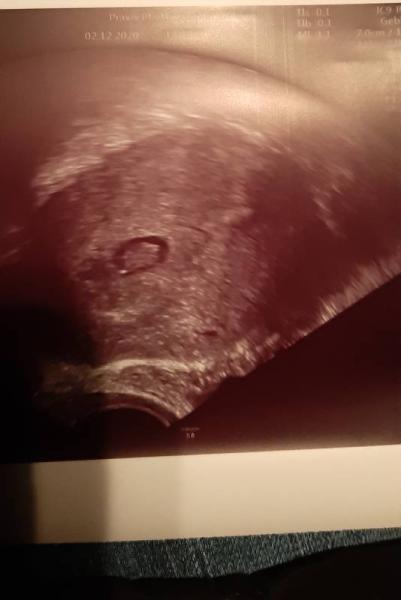

Hallo Bin heute 8+1 war gestern mal wieder beim arzt Fruchthöhle in 5 Tage nur 2 mm gewachsen. Die fruchthöhle ist nur 1 cm groß und der Embryo 3,5 mm auf 1,5 cm gewachsen mit Herzschlag. Hab solche Angst wegen fehlgeburt! Wer hat ähnliches erlebt und es ist trotzdem gut ausgegangen. Siehe Ultraschall Bild.

Bild zu Fruchthöhle klein ( 1cm ) 9ssw . - Forum für Juli - Mamis